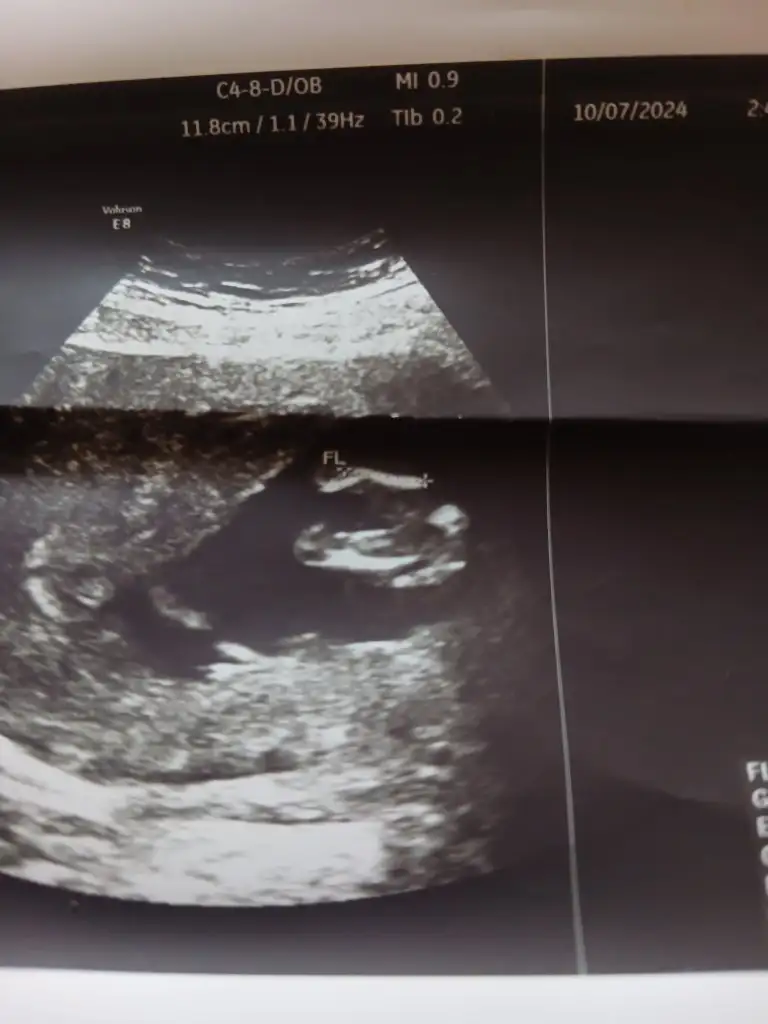

Kimse yok mu12 haftalik karindan ultrason rica etsem cinsiyet tahmini yapabilir misiniz

Başka foto yok mi12 haftalik karindan ultrason rica etsem cinsiyet tahmini yapabilir misiniz

Bacak arası fotosu bu doktor kız diyor ama ben hala erkek hissediyorummmCanım hiç belli olmuyor bacak kısımları anlayamayuz böyle

Evet doktor kız dedi ama ben ısrarla erkek hissediyorummm 14. Haftada söylediBence kız bir an öyle hissettim nedenini bilmeden ama tabi ne olursa olsun sağlıklı olsun

Evet doktor kız dedi ama ben ısrarla erkek hissediyorummm 14. Haftada söyledi

Bacak arasını boş gördüğü için demiştir kızda yanılma payı var detaylı ultrasona girene kadar bende erkek hissediyorum ama daha belli değil 15 hafta 2 günlük benim bebişim deEvet doktor kız dedi ama ben ısrarla erkek hissediyorummm 14. Haftada söyledi